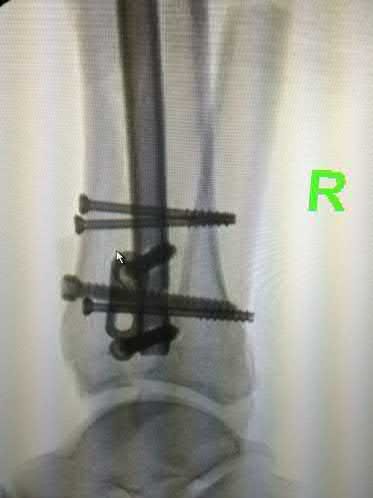

A 51-year-old carpenter presents with a distal humerus nonunion (Figures A and B). After repair of the nonunion, he is lost to follow up for 3 months and then presents to your clinic pain-free and with evidence of fracture union. On examination the elbow arc of motion is 10-80 degrees. Following a brief failed trial of conservative management, you recommend:

1) Open release of the posterior bundle of the MCL and excision of osteophytes

2) Complete open release of the MCL and LCL complexes with radiation for heterotopic ossification prophylaxis

3) Arthroscopic release of the anterior capsule with removal of hardware

4) Removal of hardware and dome osteotomy

5) Functional bracing and recommendation for job retraining

Limited flexion outside a functional range of motion (30-130 degrees) can be quite debilitating, and it is often addressed with open release of the posterior bundle of the MCL and posterior capsule and excision of osteophytes.

A frequent complication of distal humerus fractures is post-traumatic stiffness. This patient has had multiple procedures about the distal humerus, and the question stem implies that he did not complete a structured range of motion protocol following the repair of his nonunion. Beyond a trial of conservative management, there are many techniques described for capsule and soft tissue releases as well as bony resections if heterotopic ossification is present. This patient's severely limited flexion would best be addressed with a release of the posterior bundle of the MCL, and with flexion